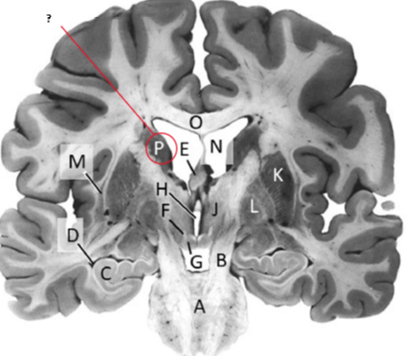

Name this and state its function.

Corpus Callosum.

Third ventricle.